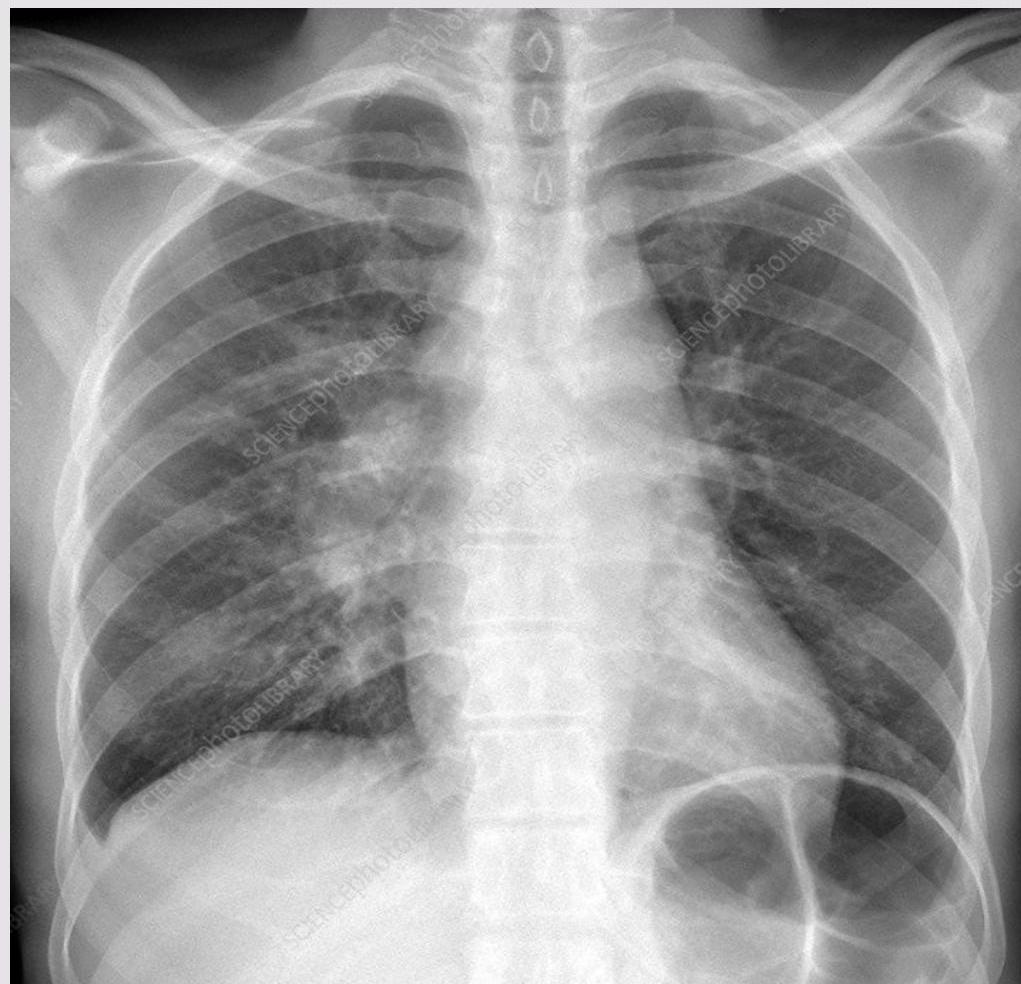

- Chest X-ray: This study will help determine the presence of mediastinal adenopathy and underlying pulmonary diseases including tuberculosis, coccidioidomycosis, lymphomas, and neuroblastoma.

Lymph node tuberculosis. Z